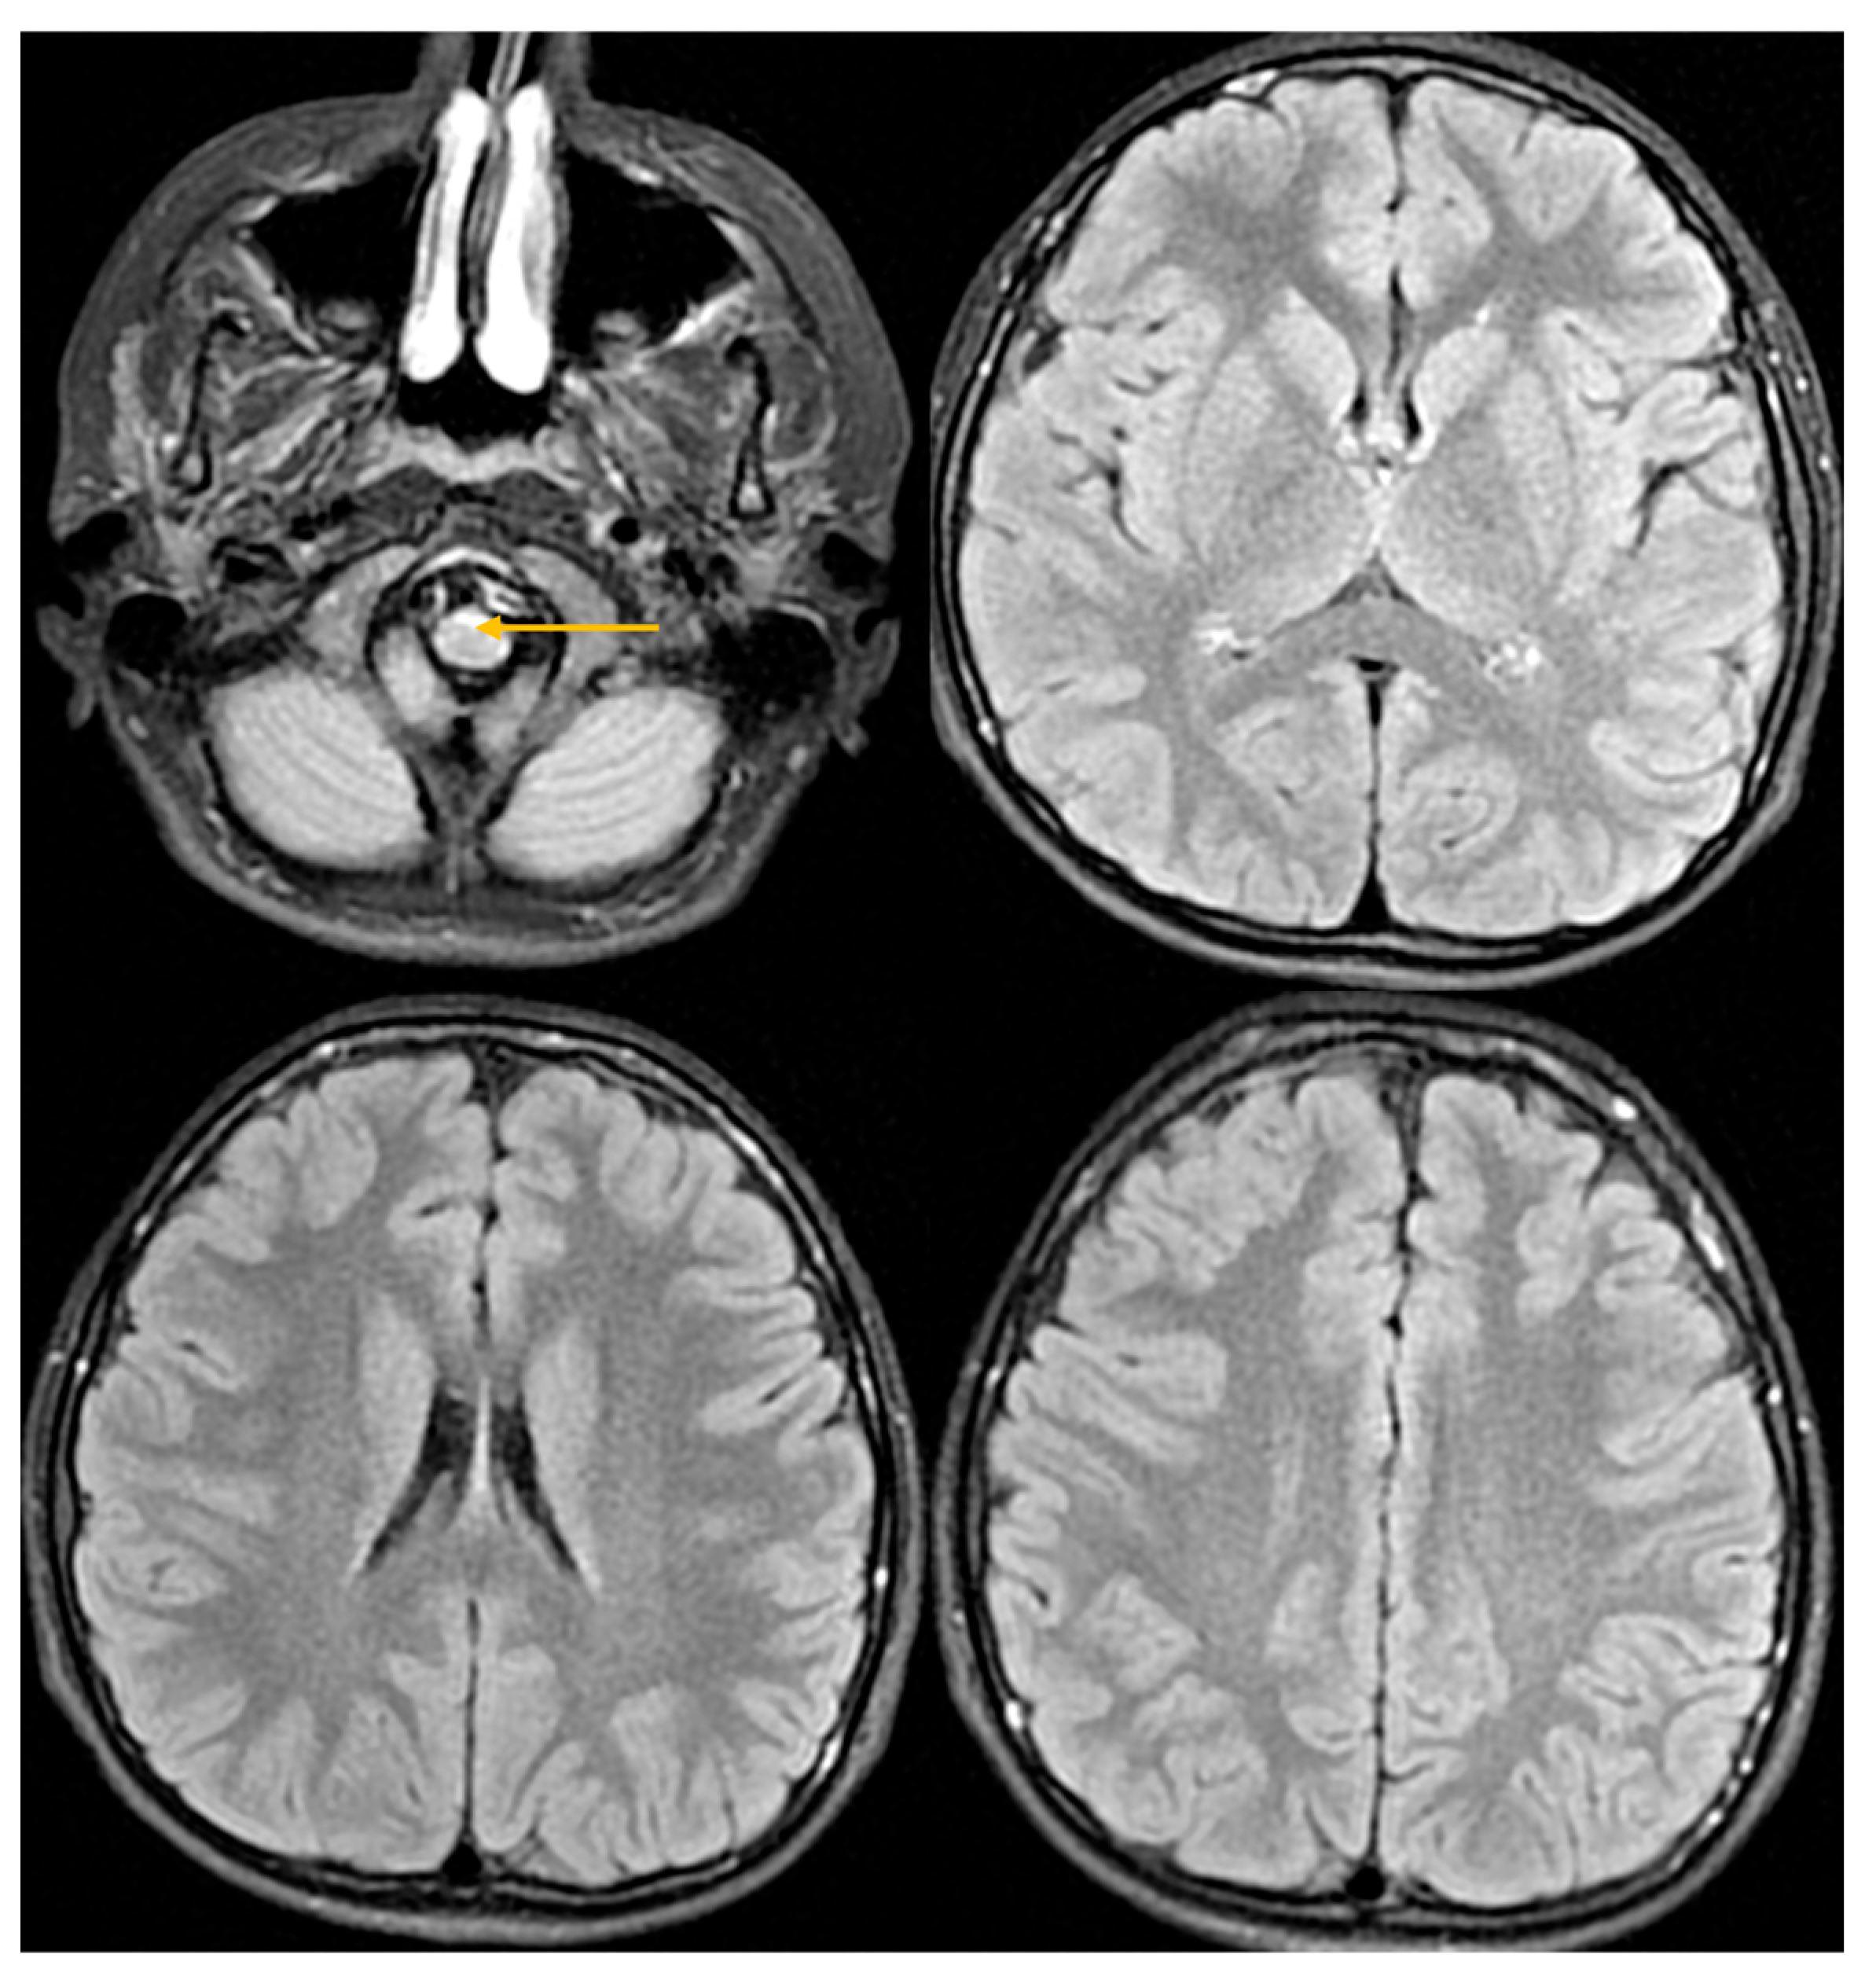

| Abnormal signal intensity of the anterior portion of the medulla oblongata | Yes | NA | Yes | Yes | Yes | Yes | Yes |

| Signal abnormalities in the cerebellar white matter or hilus of the dentate nucleus | No | NA | No | No | No | No | No |

| Cyst formation in white matter around the anterior horn of the lateral ventricles | No | NA | No | No | No | No | No |

| Ventricular garlands | No | NA | NA | NA | NA | NA | NA |

- Neuroimaging characteristics